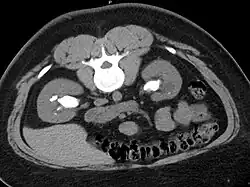

Otherwise a noncontrast helical CT scan with 5 millimeters (0.2 in) sections is the diagnostic method to use to detect kidney stones and confirm the diagnosis of kidney stone disease.[13][47][51][52][7] Near all stones are detectable on CT scans with the exception of those composed of certain drug residues in the urine,[53] such as from indinavir. Calcium-containing stones are relatively radiodense, and they can often be detected by a traditional radiograph of the abdomen that includes the kidneys, ureters, and bladder (KUB film).[53] Some 60% of all renal stones are radiopaque.[51][54] In general, calcium phosphate stones have the greatest density, followed by calcium oxalate and magnesium ammonium phosphate stones. Cystine calculi are only faintly radiodense, while uric acid stones are usually entirely radiolucent.[55]

- Bilateral staghorn calculi as seen on CT